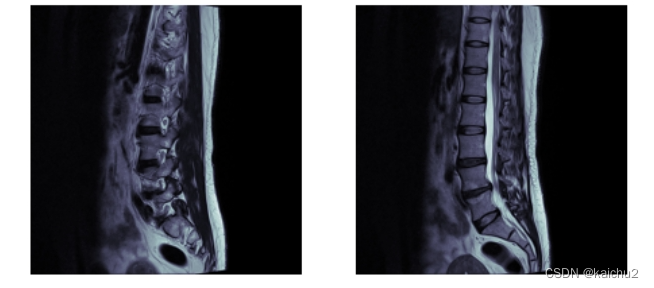

本次竞赛的目标是使用腰椎MR图像来帮助检测和分类退行性脊柱疾病。

根据世界卫生组织的数据,腰痛是全球残疾的主要原因,2020年将影响6.19亿人。大多数人在一生中的某个时候都会经历腰痛,其频率随着年龄的增长而增加。疼痛和活动受限通常是颈椎病的症状,这是一组退行性脊柱疾病,包括椎间盘退变和随后的椎管变窄(椎管狭窄)、关节下隐窝或神经孔,并伴有对下背部神经的压迫或刺激。

磁共振成像(MRI)提供了腰椎椎骨、椎间盘和神经的详细视图,使放射科医生能够评估这些疾病的存在和严重程度。这些疾病的正确诊断和分级有助于指导治疗和潜在的手术,以帮助缓解背痛,改善患者的整体健康和生活质量。

Axial T2: 轴向T2加权成像是一种MRI扫描序列,它对组织的T2弛豫时间敏感。这种序列可以提供高对比度的图像,特别是对于水分含量较高的组织,如脑脊液、肌肉和肿瘤。

Sagittal T1: 矢状T1加权成像也是一种MRI扫描序列,它对组织的T1弛豫时间敏感。这种序列可以提供高对比度的图像,特别是对于脂肪和钙化等物质。

Sagittal T2/STIR: 矢状T2/短TI反转恢复(STIR)成像是一种MRI扫描序列,它结合了T2加权成像和STIR技术。STIR技术可以抑制脂肪信号,从而提供更清晰的图像。这种序列常用于检测炎症、水肿和肿瘤等病变。